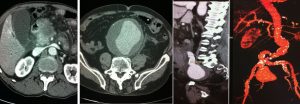

La TAC o TC, acronimo di Tomografia Assiale Computerizzata, è una metodica diagnostica medica che sfrutta le radiazioni ionizzanti (raggi X) per ottenere immagini dettagliate ed in versione tridimensionale, di aree anatomiche del corpo umano. L’esame viene eseguito dal Tecnico di Radiologia Sanitaria (TSRM) che su indicazioni del Medico Radiologo stabilisce il protocollo di esecuzione ottimale al fine diagnostico ed alla riduzione della dose radiogena di esposizione. L’interpretazione dei risultati da essa derivanti spetta al Medico Radiologo.

Le apparecchiature TC di ultima generazione hanno il vantaggio di scansionare ampie regioni corporee in pochi secondi e di effettuare un gran numero di ricostruzioni nel post-processing.

La Tc utilizza come fonte di energia i raggi X, come la radiologia convenzionale; tuttavia mentre la classica immagine radiografica è il risultato della trasformazione analogica o digitale di una realtà tridimensionale in bidimensionale, nella TC l’immagine è oggetto di una trasformazione di tipo digitale che permette di mantenere la tridimensionalità del distretto osservato.

Grazie alla elevata qualità delle immagini che è in grado di fornire, la TC permette di studiare lo stato di salute degli organi interni (es: cervello, reni, fegato, polmoni, cuore ecc), delle ossa, dei vasi sanguigni e dei linfonodi. In particolare, la TAC è un valido supporto all’individuazione di:

Le ricostruzioni 3D, VR e MIP sono particolarmente utili non solo nel rappresentare lo scheletro e quindi le fratture complesse ma anche nello studio accurato delle strutture vascolari e degli organi profondi. Un particolare software permette di ottenere delle dettagliate immagini di tipo endoscopiche trova impiego nella colonscopia virtuale e anche nella broncoscopia virtuale, esami particolarmente utili soprattutto quando l’esame endoscopico non puo essere eseguito o quando viene interrotto. Altra fondamentale applicazione è la TC ad alta risoluzione del polmone, un esame che viene acquisito o successivamente ricostruito con precisi parametri dedicati per lo studio delle più fini strutture polmonari utile nello studio delle patologie interstiziali polmonare (HRTC).

- Addominale: consente una valutazione attenta dello stato di salute degli organi e vasi sanguigni del comparto addominale e pelvico.

- Angio TC: particolare variante della TC con contrasto che focalizza le attenzioni sulla circolazione sanguigna all’interno dei vasi sanguigni arteriosie venosi del corpo.